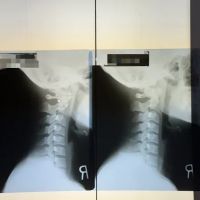

Thorough Diagnostic Assessments: A hallmark of their service is the initial in-depth assessment, including taking an X-ray "before starting any treatment to pinpoint exactly what needed to be fixed." This detailed approach ensures that treatments are precise and targeted to the root cause of the patient's condition.

Dr. Park's Exceptional Skill and Meticulous Approach: The most significant highlight is the expertise of Dr. Park, consistently lauded as "the Best!" Patients appreciate his "very thorough" initial assessment, including X-rays, to "pinpoint exactly what needed to be fixed." This detail-oriented approach ensures that treatments are incredibly precise and effective, leading to significant and lasting improvements, even for complex injuries.

Firstly, the expertise of Dr. Park, frequently lauded as "the Best!" and a "skilled, caring, and detail-oriented" practitioner, is a major draw for locals. In a city where health and wellness are highly prioritized, finding a chiropractor who conducts a "very thorough" initial assessment, including X-rays, to "pinpoint exactly what needed to be fixed," ensures that patients receive precise and effective care. This level of diagnostic accuracy is crucial for treating complex conditions like serious back injuries or shoulder dislocations from accidents, leading to faster and more complete recoveries.

Apr 16, 2025 · Leo MiguelExceptional Chiropractic Care – Dr. Park is the Best!I had a shoulder dislocation and a misaligned spine due to an accident, and Dr. Park at Yonsei Chiropractic truly helped me recover. From the beginning, he was very thorough, taking an X-ray before starting any treatment to pinpoint exactly what needed to be fixed. He explained everything clearly, which made me feel confident and reassured throughout the process.The adjustments were precise, and I could feel the improvement after each visit. Now, my shoulder and spine feel so much better. The clinic is clean, well-organized, and has a welcoming atmosphere. The staff is also very friendly and professional.If you’re looking for a chiropractor who is skilled, caring, and detail-oriented, I highly recommend Dr. Park. Five stars all the way!

Mar 07, 2025 · Mijeong KimThis clinic is life-changing! I came here following a car accident with neck and back pain. The entire process was seamless, from completing paperwork to getting X-rays. Every question I had was thoroughly answered, making me feel well-informed and cared for. The Dr. Park is highly professional and kind, and the treatment room is clean, inviting, and enhanced by soothing classical music. After almost 3 months of sessions, I am sleeping better and my neck and back pain have subsided thanks to Dr. Park. Scheduling is flexible, and they even validate parking, which is a great bonus. I couldn’t be happier with my experience—10/10, highly recommend!Update: I recently completed my treatment at this clinic, and I truly wish I had more sessions! The chiropractor was fantastic—extremely knowledgeable, professional, and kind. Throughout my treatment, I made great progress; my neck pain has significantly improved, and I can finally sleep through the night again. The entire experience, from the smooth intake process to the welcoming atmosphere with soothing classical music, was outstanding. Scheduling was always flexible, and the fact that they validate parking was a great convenience. I highly recommend this clinic to anyone in need of chiropractic care—10/10!